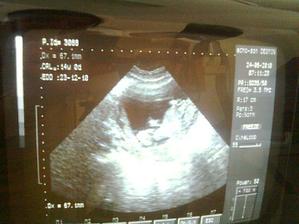

Náš anjelik🙂